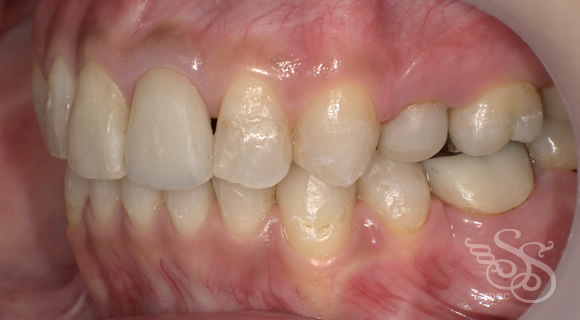

修復物が多い方の矯正

口元:術前

左側:術前

左側:術後